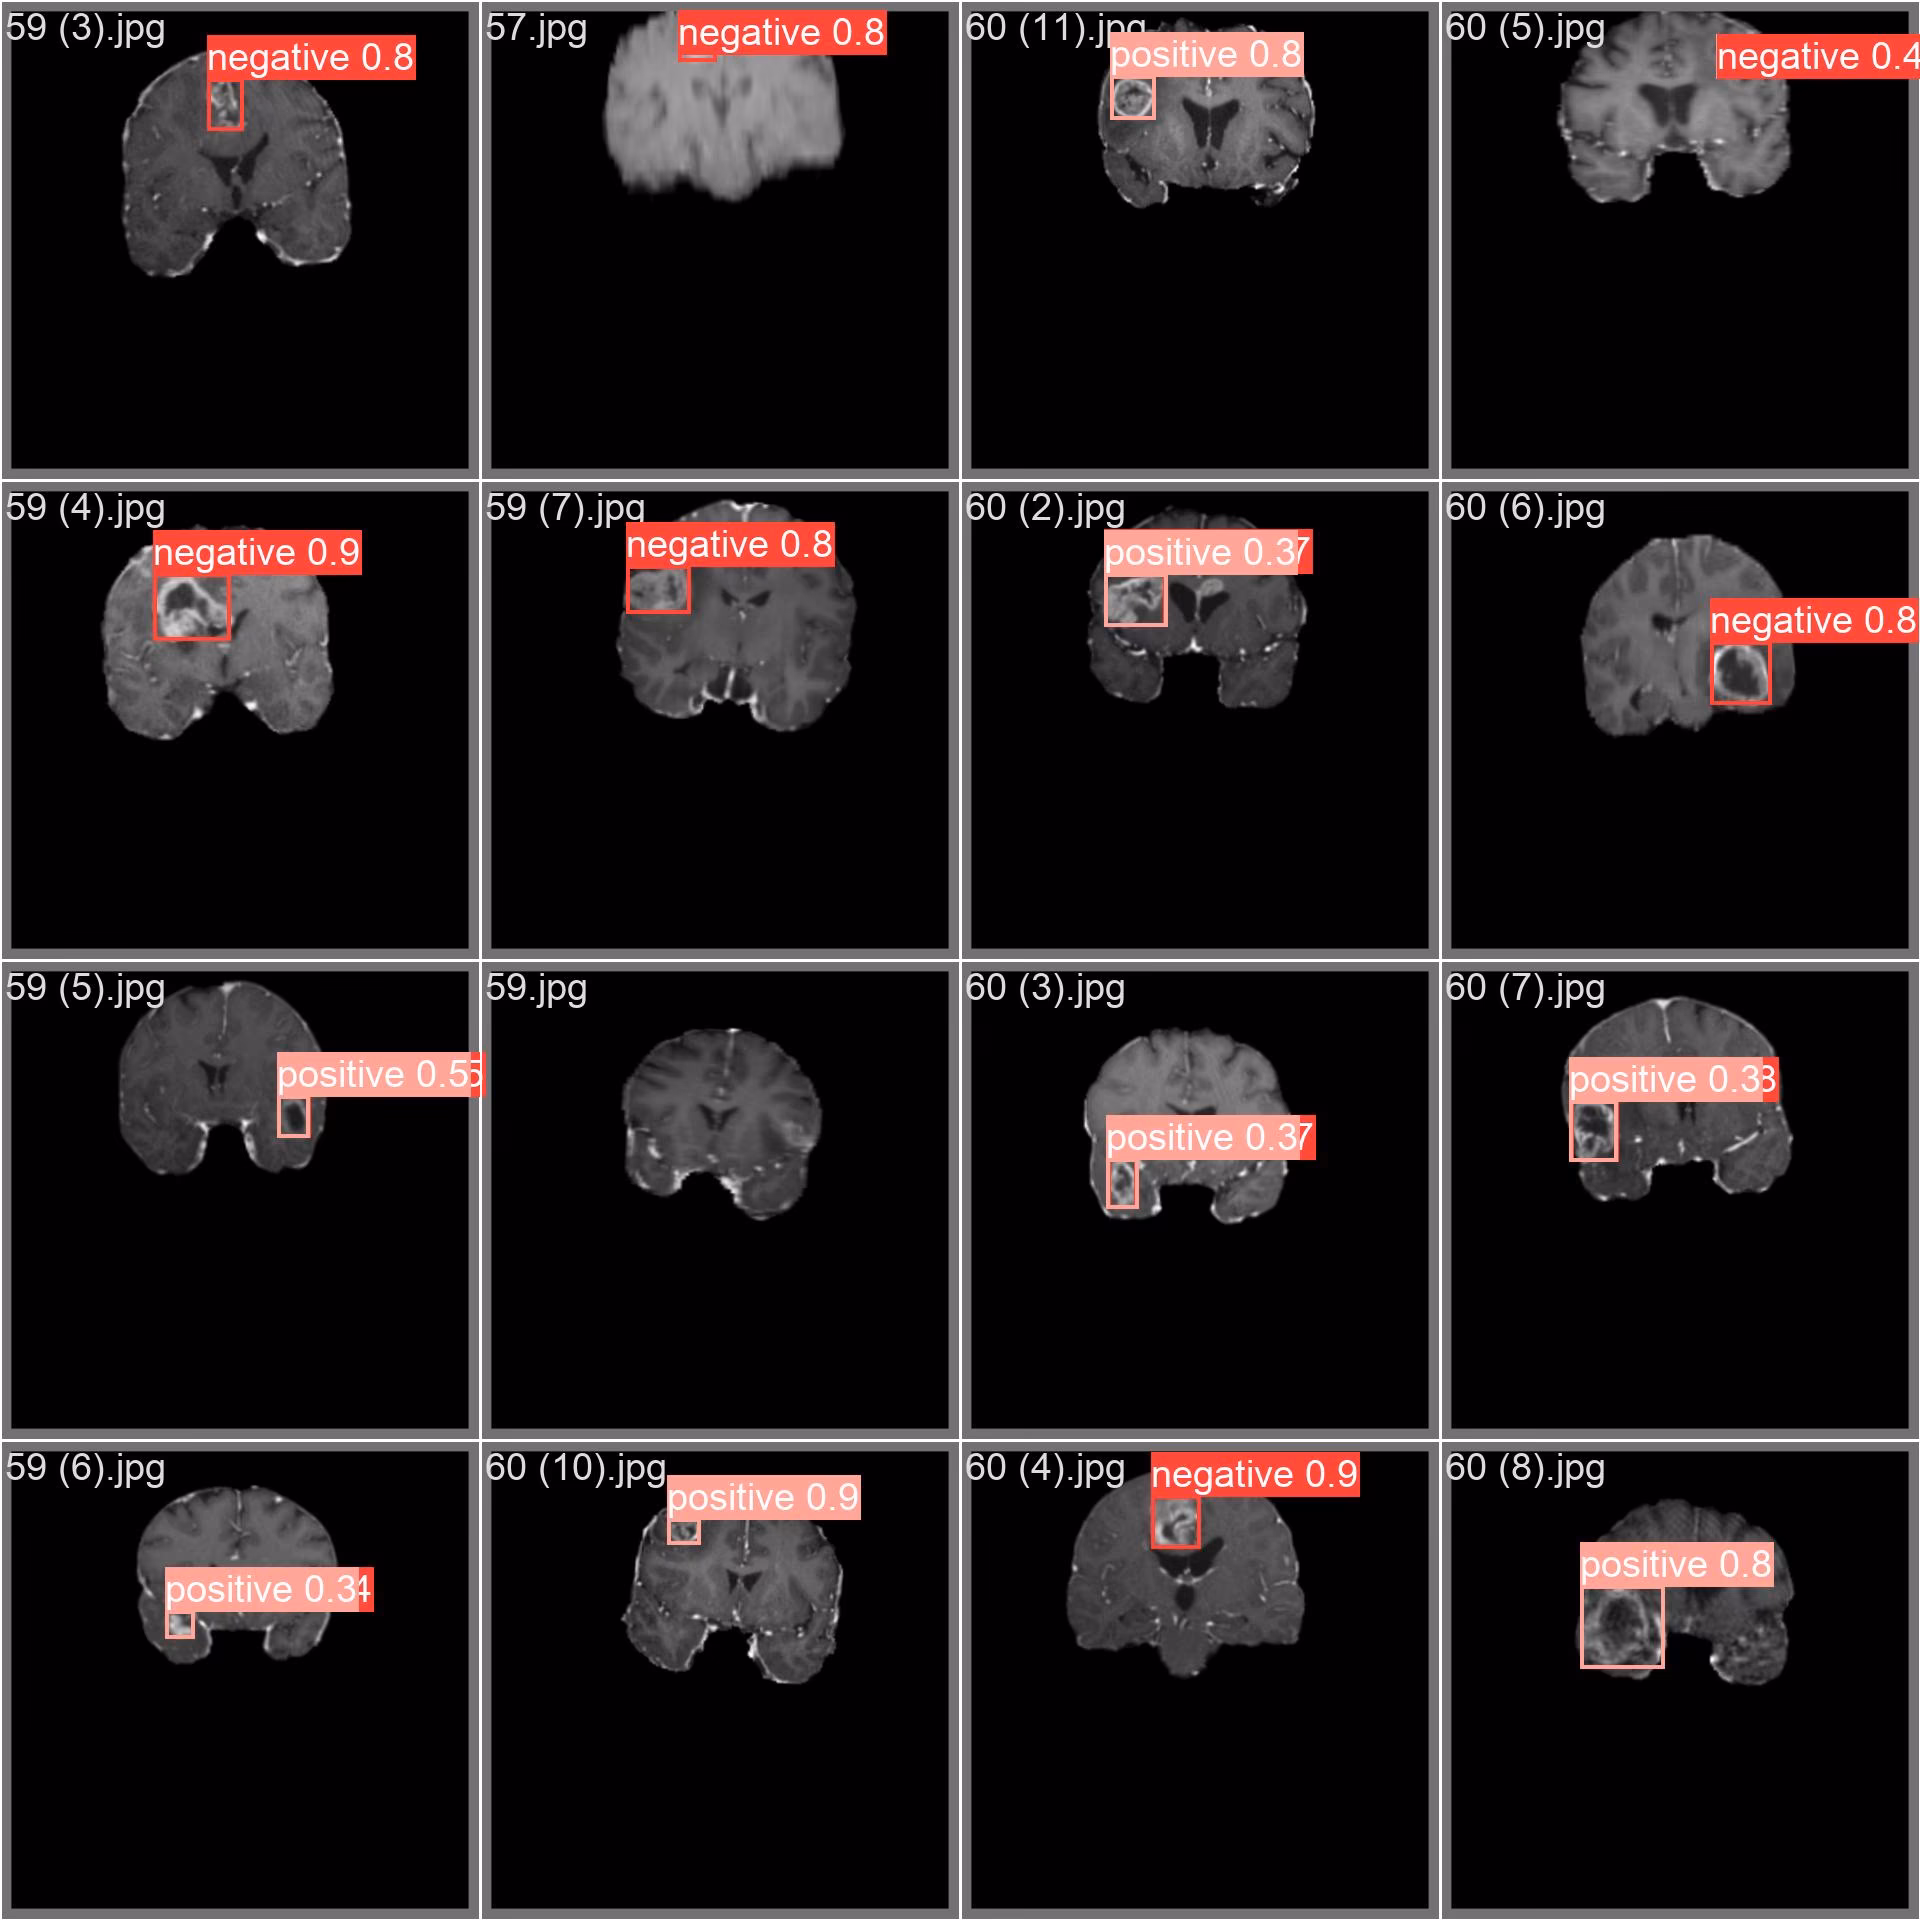

Sample Images 和注释

脑肿瘤数据集包含大量医学图像,其中包含有肿瘤和无肿瘤的脑部扫描。下面展示了数据集中图像的示例,并附有相应的注释。

- 马赛克图像: 这里展示的是一个包含马赛克数据集图像的训练批次。马赛克处理是一种训练技术,它将多个图像合并为一个图像,从而增强批次的多样性。这种方法有助于提高模型在脑部扫描中对各种肿瘤大小、形状和位置的泛化能力。

此示例突出显示了脑肿瘤数据集中图像的多样性和复杂性,强调了在医学图像分析的训练阶段中加入镶嵌的优势。